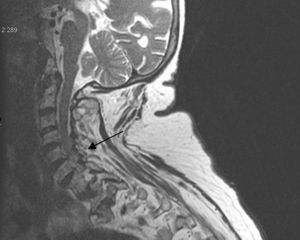

X-ray studies show cervical spondyloarthritis and calcification of the transverse ligament of the atlas and winged ligaments of the atlas-axis joint (Fig. 4).

The Crowned Dens syndrome was described initially in 1985 by Bouvet et al.1,2 Diagnosis is based on the association of a compatible clinical picture and imaging findings, mainly calcium deposits in atlas-axis joint ligaments, visible on CT.3,4